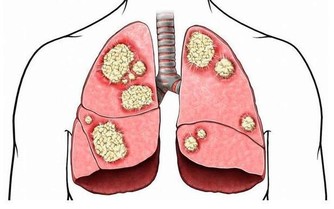

終於找到害她肩背疼痛的「元兇」——胰腺癌。

醫生說,這些症狀已經在提示姚女士胰腺壞了。

胰腺疾病不容易發現,如果能早點注意到發病信號,對治療很有幫助。